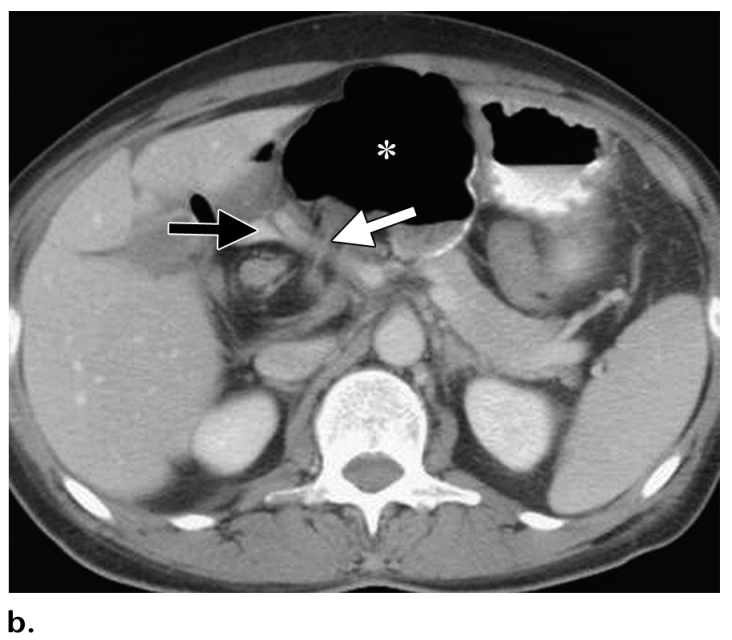

What is Happening here?

What is the anatomy involved?

Foramen of Winslow Hernia

Axial CT image obtained in a 48-year-old woman shows the cecum (*) adjacent to the stomach, an unusual position, and passage of the right colic vessels (white arrow) across the foramen of Winslow, findings indicative of a foramen of Winslow hernia.

The foramen is marked posteriorly by the hepatic vessels (black arrow).

The presence of a foramen of Winslow hernia was confirmed at surgery.